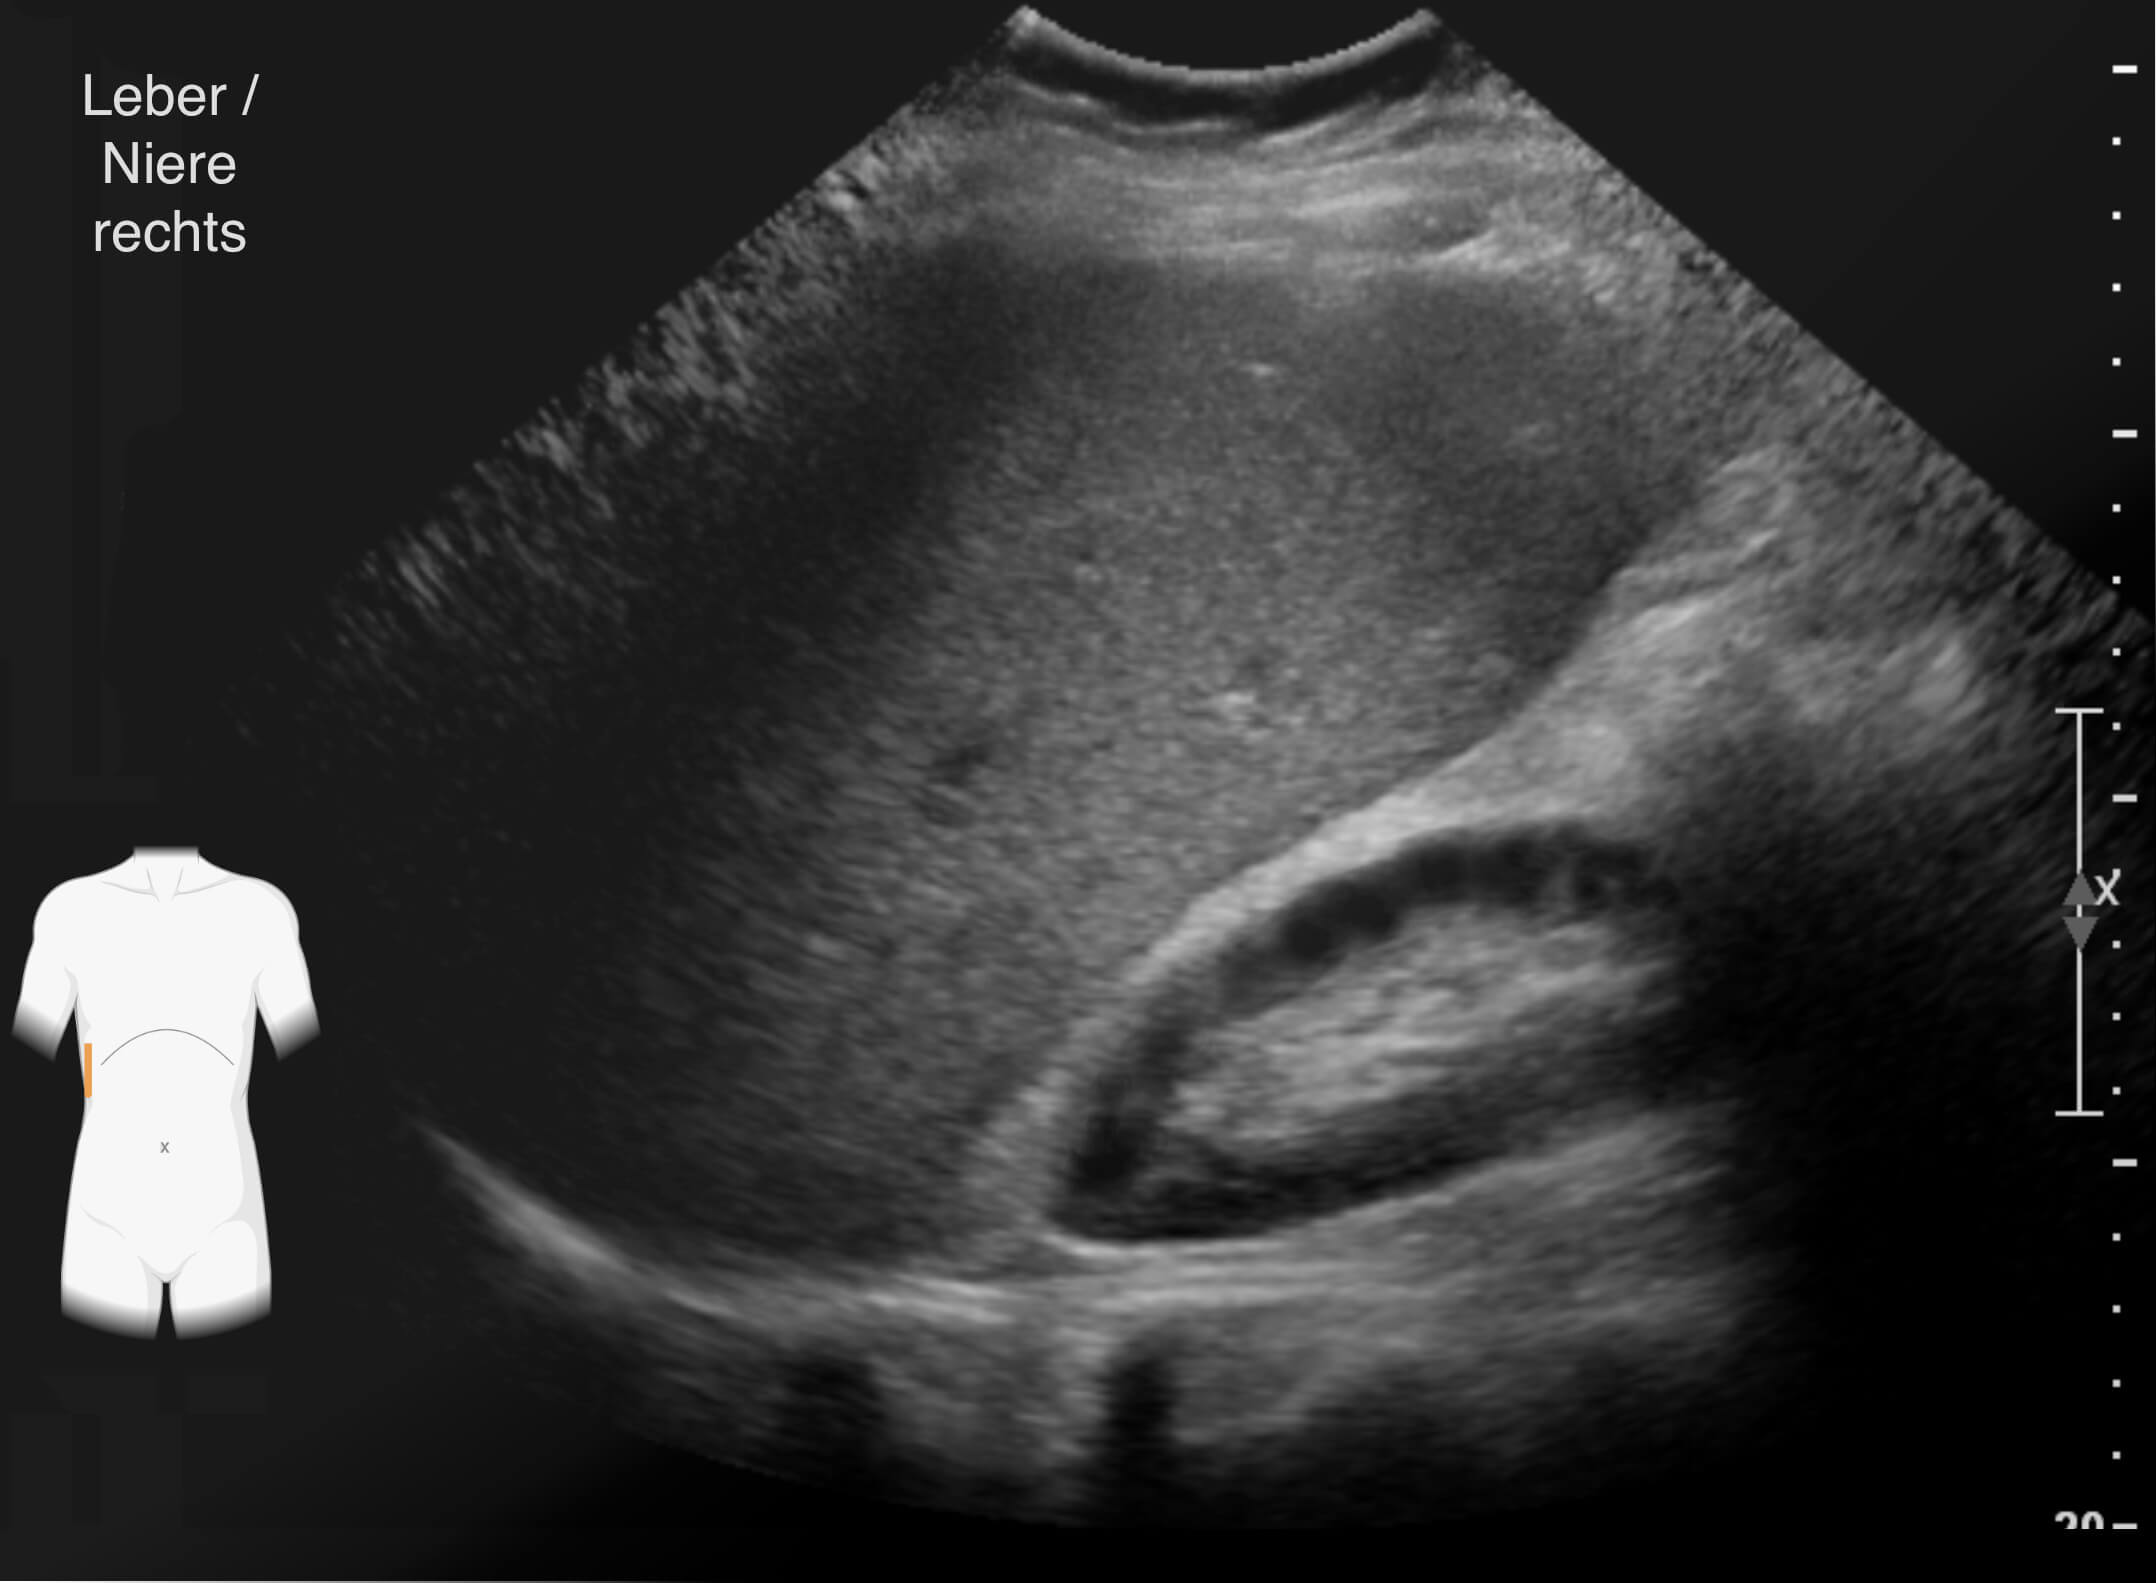

Die Ergebnisse der durchgeführten Untersuchungen kannst du dir hier anschauen:

Die Befunde geben eindeutige Hinweise auf die Erkrankung von Frau Lorenz. Wie bewertest du die Ergebnisse?